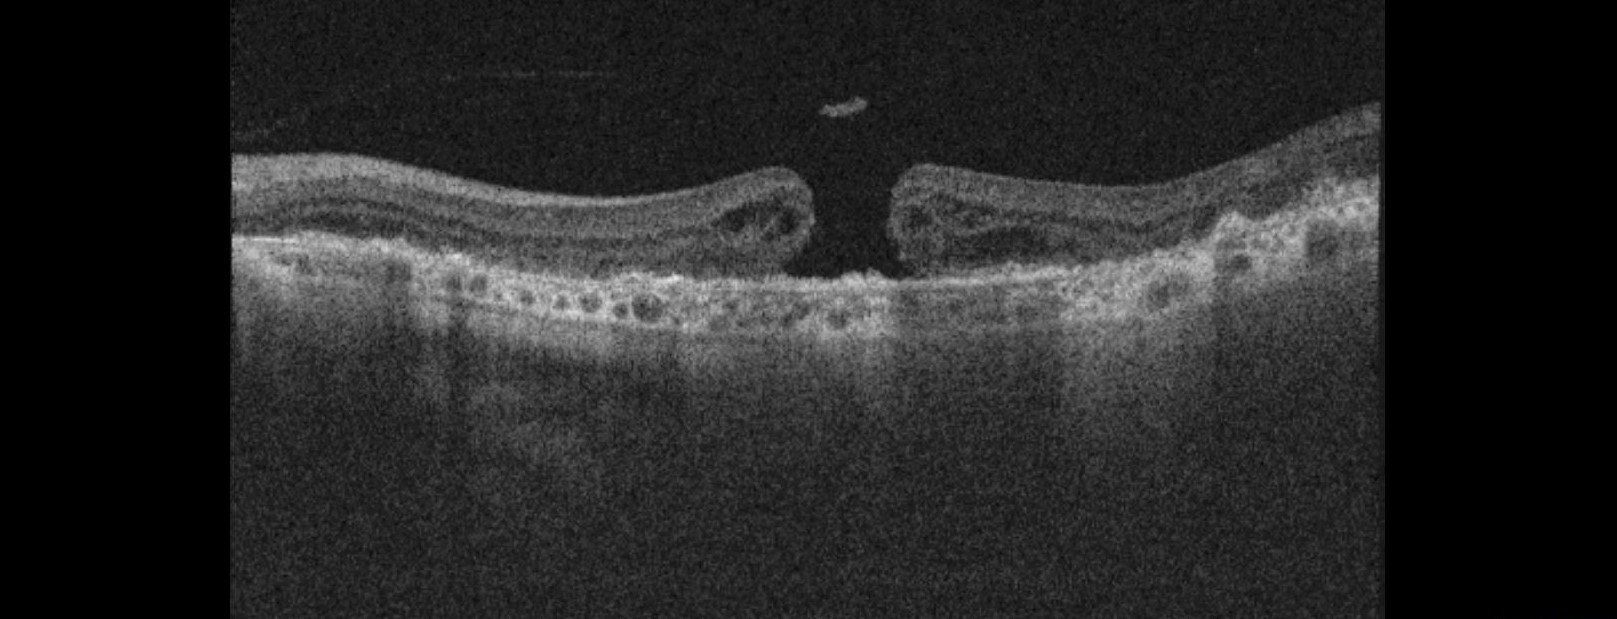

Epiretinal membrane -This is where the layer on the surface of the retina ‘wrinkles’. Patients may experience no symptoms at all, blurring or even distortion in their vision.